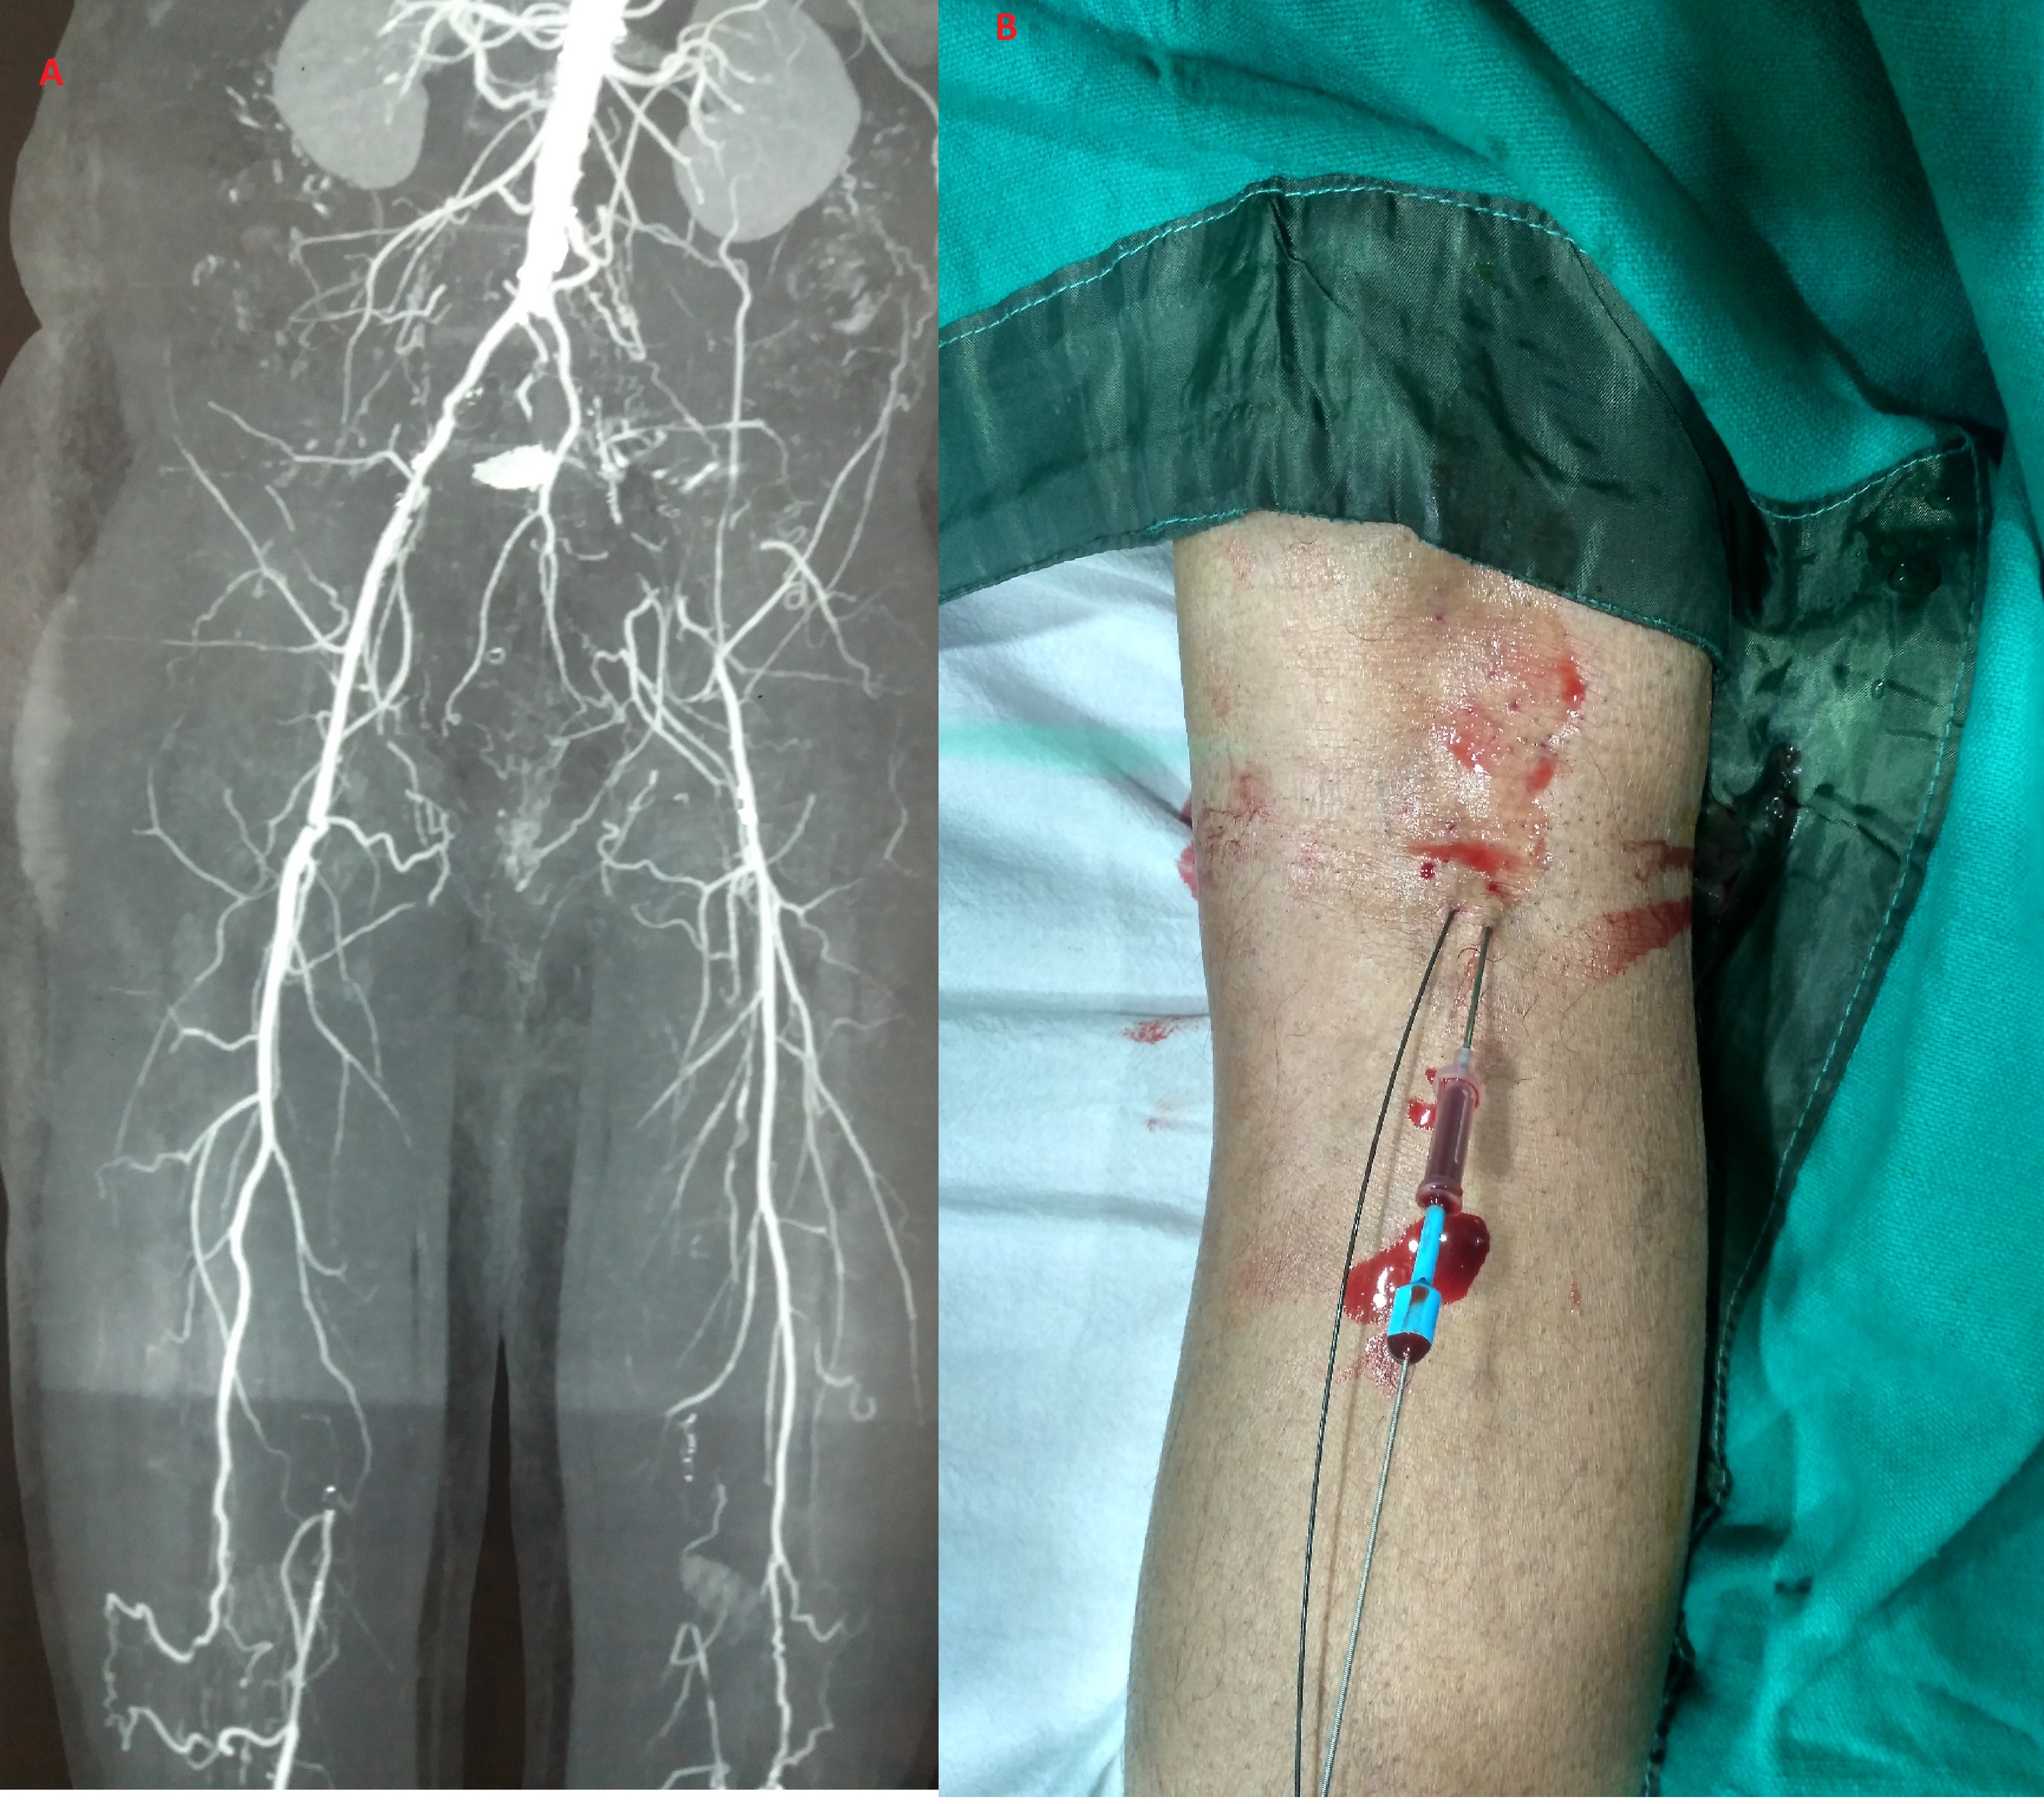

A 58-year-old man presented with right lower-extremity claudication at rest with Rutherford grade 4 ischemic atrophy of the right foot despite several attempts at debridement, as well as amputation of the great toe of the right lower limb. He did not have diabetes and did not smoke. The patient underwent peripheral arterial Doppler, which revealed significant atheromatous disease of both lower-limb arteries. Computed tomography (CT) of the abdominal aorta and lower limbs was done with contrast enhancement (Figure 1A), and the juxtarenal aorta and infrarenal aorta had mild disease. Both renal arteries were normal. CT angiogram showed total occlusion of the external iliac artery, common iliac artery, and almost the entire length of the superficial femoral artery (SFA), except at its far distal segment. Ankle brachial index was 0.8 in the left lower limb and 0.4 in the right lower limb. CT angiogram of the left lower extremity revealed the total occlusion of the entire length of the femoral artery except at its distal part with robust collaterals from the profunda femoris artery.

With aseptic measures, local anesthesia, and proper counseling, an attempt was made to enter the distal SFA using the 18 gauge needle (Cook Medical) via retrograde popliteal access. At the first attempt, the routine 18 gauge needle entered the distal part of the great saphenous vein, which was confirmed by the follow-up of the course of iodinated contrast and Terumo guidewire (Figure 1B), which helped us immediately access the distal SFA. A 6 Fr sheath was introduced into the distal SFA via the popliteal artery. AB The opening pressure waveform was 60 mm Hg. As this patient was already taking clopidogrel, cilastazole, and a statin, a bolus of 5000 IU unfractionated heparin was given.